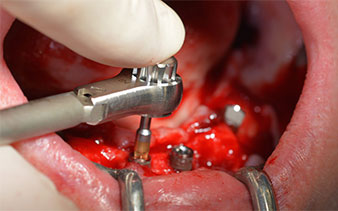

Das chirurgische Protokoll der verwendeten Implantate (SKY, bredent medical) schreibt eine Umdrehungszahl von 1.200/min für die Pilotbohrungen vor (Abb. 7–9).

Dies entspricht der nächsten Position der Voreinstellung am Implantmed. Zu erkennen ist die etwa 45-Grad-Schräghaltung des W&H Winkelstückes nach mesiokaudal in Regio 45, um den Nervus mentalis zu schonen. Das Foramen mentale gilt als anatomische Orientierung für alle Bohrungen in diesem Bereich. Die anschließenden Bohrungen werden mit einer reduzierten Umdrehungszahl von 300/min durchgeführt (Abb. 10 und 11).